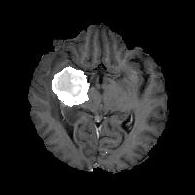

(a) (b) (c) (d)

Boundary Stream:

Fig. 2 demonstrates the output of each of the attention layers in our dedicated boundary stream. In essence, each attention layer progressively localizes the tumor and refines the boundaries. The first attention layer has learned rough estimate of the boundaries around the tumor and localized it, whereas the second and third layers have learned more fine-grained details of the edges and boundaries, refining the localization. Moreover, since our architecture leverages a dilated spatial pyramid pooling to merge the learned feature maps of the regular segmentation stream and the boundary stream, multiscale regional and boundary information have been preserved and fused properly, which has enabled our network to capture the small structural details of the tumor.